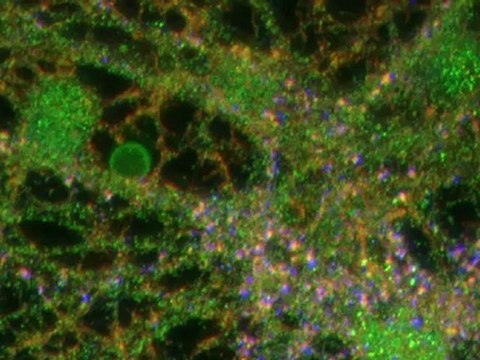

La en­fer­me­dad del Pár­kin­son es un pa­de­ci­mien­to con ori­gen des­co­no­ci­do en la ma­yor par­te de los ca­sos. Es una en­fer­me­dad neu­ro­de­ge­ne­ra­ti­va pro­du­ci­da por la muer­te de neu­ro­nas en una par­te del ce­re­bro que se co­no­ce como sus­tan­cia mi­cro com­pac­ta. Nota: noticiasncc.com/cartelera/articulos-o-noticias/09/27/parkinson-como-tratar-esta-enfermedad-neurodegenerativa/